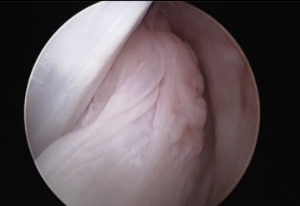

(左)ニューファンドランド50kg

前十字靭帯部分断裂 正常な後十字靭帯(左)の右横に隣接して見えている部分断裂のため腫れている前十字靭帯